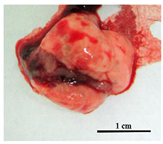

| Rostov | ~50% | Extreme emaciated, hunched posture, “ruffled” fur, reduced movement | ![]() Intensively hyperemic, no visible nodules | ![]() Dark brown with multiple nodules, fatty degeneration |